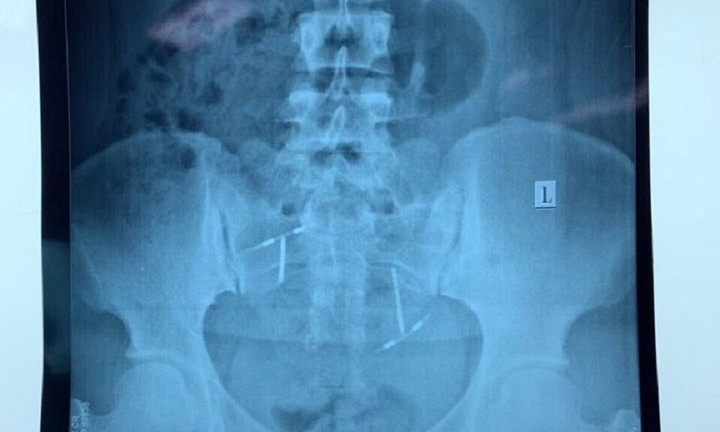

Vòng tránh thai ‘đi lạc’ trong bàng quang người phụ nữ ở Quảng Nam

Trải qua ca phẫu thuật kéo dài cả tiếng đồng hồ, các bác sĩ lấy thành công vòng tránh trai lạc chỗ trong bàng quang của một phụ nữ ở Quảng Nam.